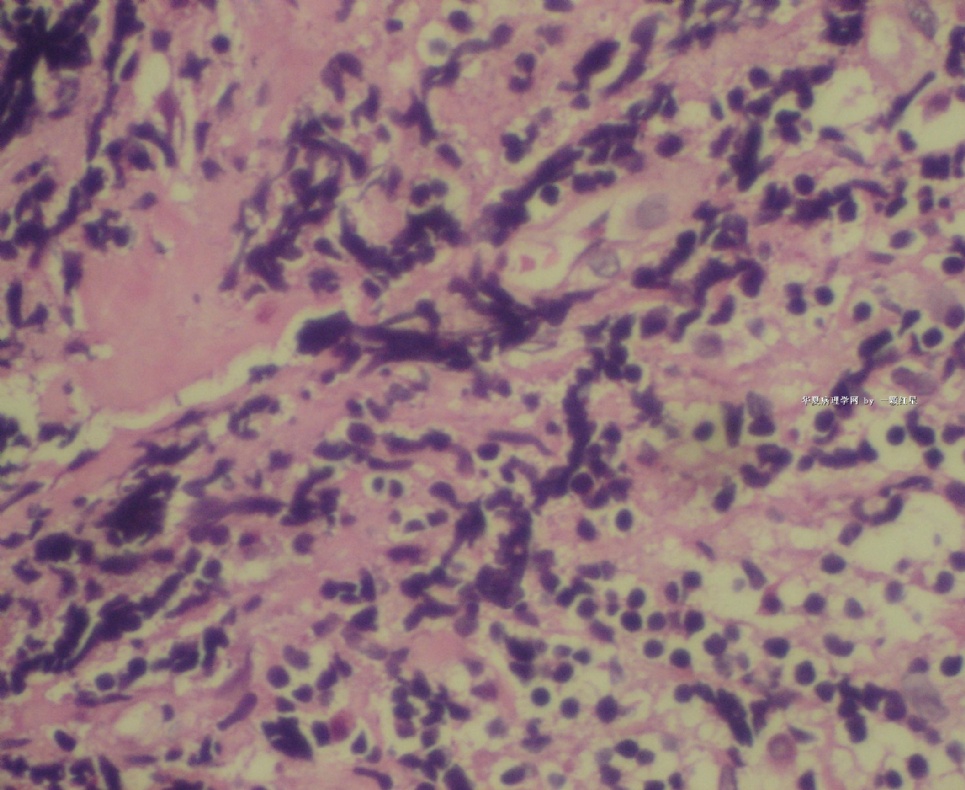

标本名称:  左前臂数个大小不等的皮下肿物。

既往有非何杰金淋巴瘤(滤泡性淋巴瘤)病史22个月。

• 左前臂数个大小不等的皮下肿物     淋巴瘤?图2

图2

病例不错。细胞胞浆透亮,间质血管丰富,图片不是很清晰,似乎有嗜酸粒细胞?

恶性,首先考虑T-NHL。IHC证实。

既往有NHL病史,图片不太清晰,细胞弥漫,胞浆透亮,首先考虑T细胞淋巴瘤。